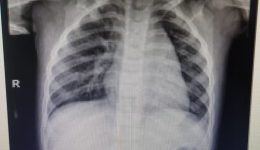

险!2岁孩子误吞硬币、电池?别用土方法!